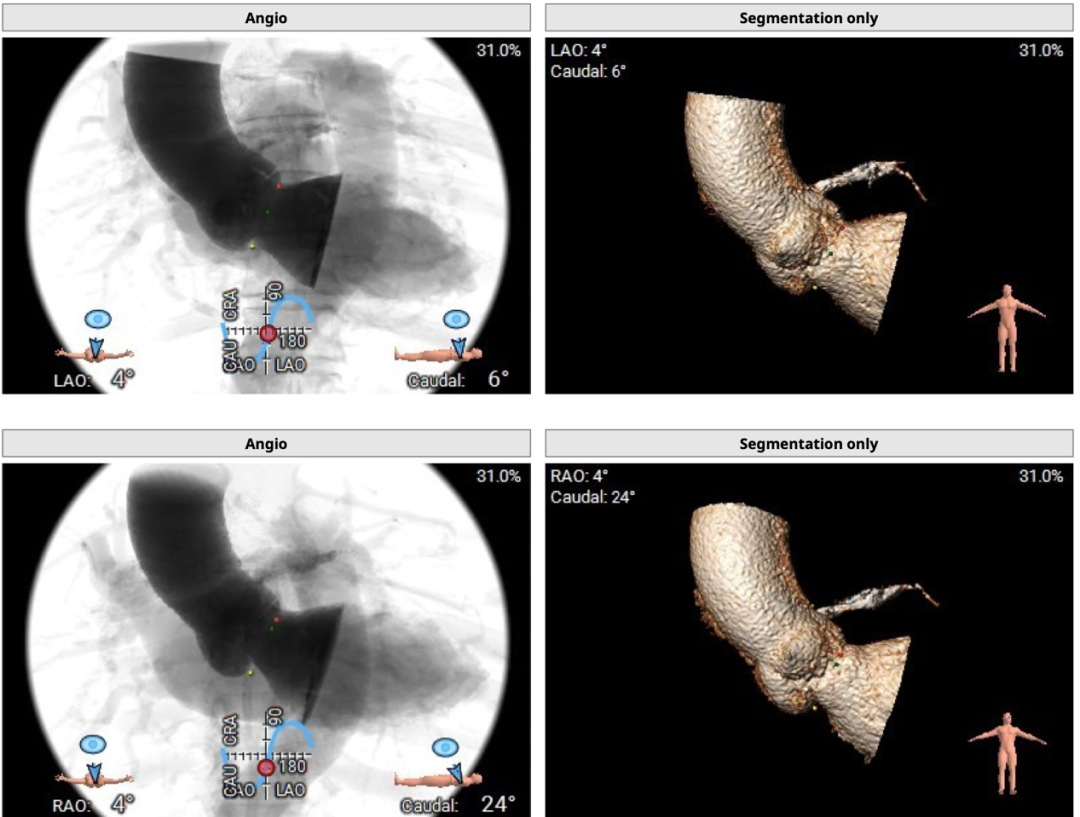

术中建议造影角度LAO 4°,CAU 6°(其它考角度如下图):

横位心,心室角度68°: